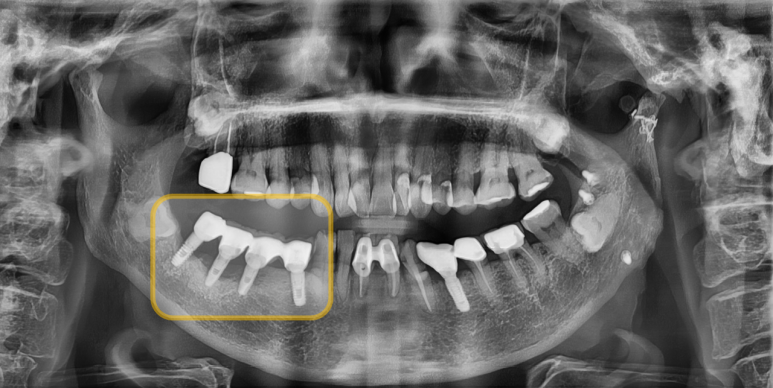

임플란트 주위염이 발생한 우측 아래 연결된 임플란트

(치과 X-ray 사진은 보통 좌우가 반대로 되어 있습니다.)